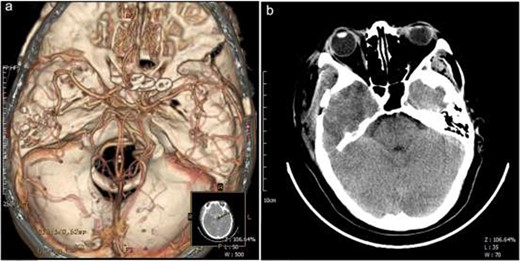

A 52-year-old female patient was admitted to the neurosurgery department of our hospital for a recurring headache, dizziness, and the appearance of a black shadow in the right eye experienced over 1 month. The patient had a history of hypertension, long-term use of amlodipine benzenesulfonate tablets, and self-reported blood pressure control. She was unable to tolerate magnetic resonance imaging (MRI). An enhanced computed tomography (CT) scan of her head revealed a clear circular shadow in the right temporal region of the brain. The shadow contained a diameter of ~ 1.9 cm and lesions were apparent with no obvious signs of edema. CT angiography (CTA) revealed small saclike projections in the supraocular segment of the bilateral internal carotid artery with diameters of ~ 0.3 cm. A digital subtraction angiography (DSA) revealed a cystic shadow with a size of ~ 3.2 × 3.8 mm and a cervical width of ~ 2.4 mm visible in the ophthalmic segment of the right internal carotid artery protruding upward and outside the vascular lumen. The left ophthalmic artery, showing a size of ~ 3.0 × 4.2 mm and a cervical width of ~ 2.6 mm, was seen at the beginning of the lobulated cyst-like process from outside of the lumen. The ophthalmic artery rose from below the neck of the aneurysm (Fig. 1a–d).

Preoperative imaging. axial CT demonstrated a clear circular shadow with a diameter of ~ 1.9 cm (a). A presurgical CTA revealed small cystic projections in the supra segment of the bilateral internal carotid artery bed process with a uniform diameter of 0.3 cm (b). Presurgical DSA revealed a cystic shadow that was visible in the ophthalmic segment of the right internal carotid artery protruding outside of the vascular lumen. The left ophthalmic artery was visible at the front of the lobulated cyst-like process arising from outside of the lumen. The ophthalmic artery rose from below the neck of the aneurysm (c and d). L, left; R, right.